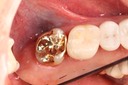

Mark Chun #17 casting

Scott Kanamori #17 prep